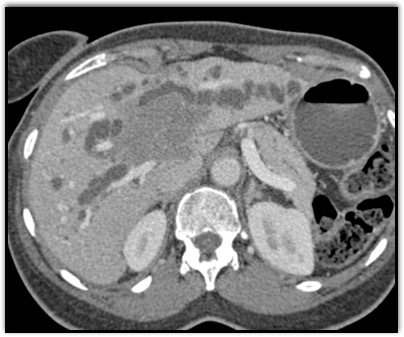

The least likely diagnosis in this case is?

lymphoma

cholangiocarcinoma

acute hepatitis

hepatoma